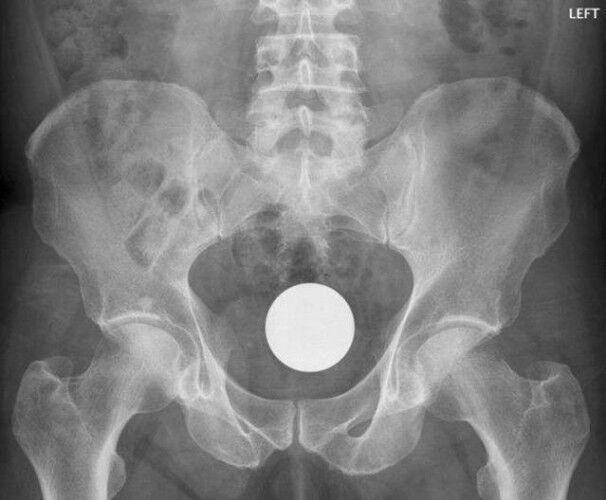

Röntgen Filminde İnsanların İçinden Çıkan Acayip Maddeler

4 / 9